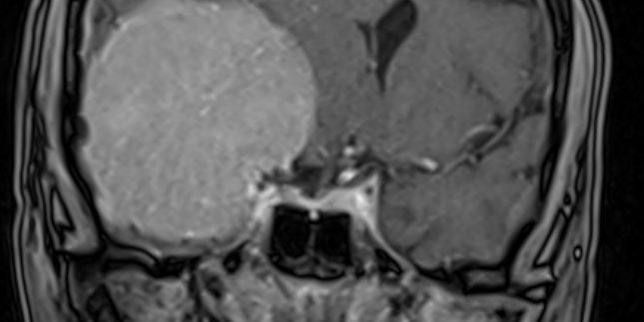

Ασθενής 69ετών με συμπτώματα βραδυψυχισμού και έκπτωση γνωσιακών λειτουργιών.

Ο απεικονιστικός έλεγχος με μαγνητική τομογραφία ανέδειξε ευμεγέθη εξεργασία δεξιά, συμβατή με μηνιγγίωμα πτέρυγας σφηνοειδούς οστού.